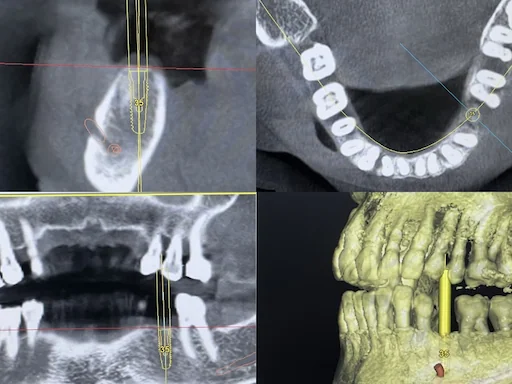

Implantologie Behandlungsbeispiel: Unterkiefer Zahn-36 - Implantatplanung

Schritt 2

Zur Untersuchung der Implantationsmöglichkeiten wurde eine Volumentomographie durchgeführt. Die sogenannte DVT ermöglicht eine exakte digitale Planung der Implantatposition.

Insbesondere im Unterkiefer ist der im Knochen verlaufende Nervus alveolaris inferior zu berücksichtigen. Dieser ist für die Sensibilität der Lippe verantwortlich. Er ermöglicht es auch, die zur Verfügung stehende Breite und damit den Implantatdurchmesser optimal zu bemessen.